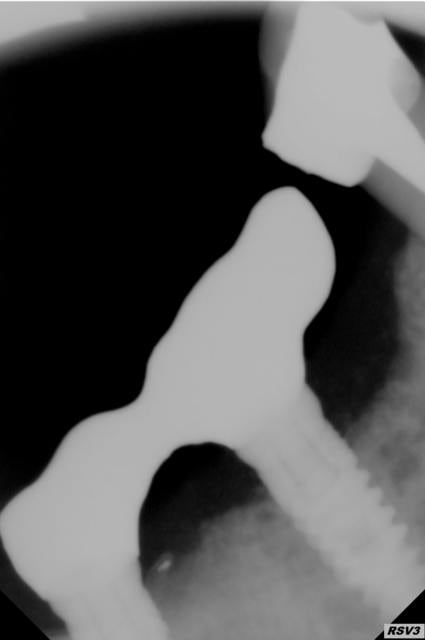

implants posés en mars 2015 patient fumeur 10 cig par jour, hygiene correcte

1 er radio le jour de la pose

2 e radio juillet 2015

3e radio fin décembre 2015

4é radio aujourd'hui soit 1 mois plus tard

au vue de la radio et des info qu'on a, cela ne semble pas être une périimplantite infectieuse. plutôt un implant mal osteointegré, ou un problème de surface.

ce qui est étonnant, c'est de trouver du ciment dans les spires..

Eh oui c'est sur ce fait que je voulais attirer l'attention comment expliquer que je retrouve du ciment aussi apicalement alors que sur les différents clichés on voit pas de signes